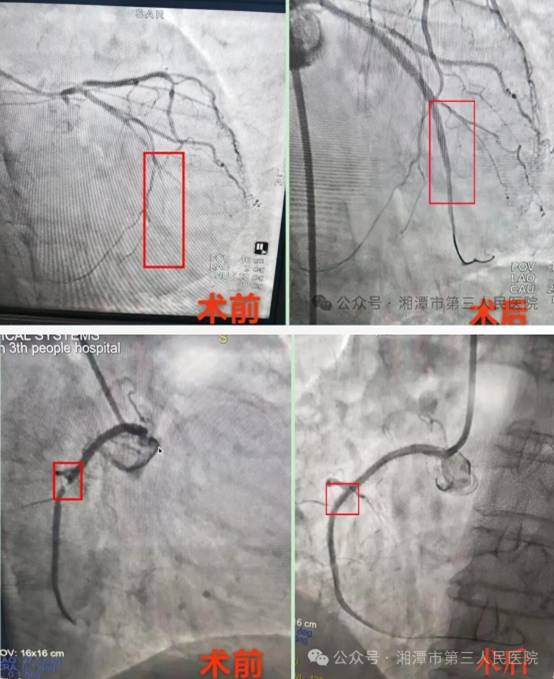

近日,心血管内科介入团队为一位75岁女性患者实施了前降支及回旋支冠脉支架植入术。

该患者曾于去年11月因急性心肌梗死在湘潭医卫职院附属医院完成右侧冠状动脉球囊扩张介入手术。术前造影检查提示,该患者心脏有三根血管有病变,当时介入团队综合评估患者病情等情况,决定实施分期手术,其他两根病变血管将于第一次介入手术后身体恢复,再择期进行介入治疗。

第一次介入手术

第一次术后患者身体恢复良好,和家人一起过了一个快乐的春节。3月中旬,患者再次突发胸闷、头晕等症状,这次家属马上将其送到心血管内科,完善相关检查后,初步诊断为急性冠脉综合征。复查冠脉造影提示右冠状动脉未见明显狭窄,未处理的左冠血管回旋支完全闭塞,前降支严重狭窄,需尽快介入治疗。经多学科专家会诊评估,决定为其实施前降支及回旋支冠脉支架植入术,由上级医院专家指导,心内科介入医生杨明峰、吴忠昊紧密协作,心内科主任胡小勇在控制间全程监测下,手术顺利完成。术后,患者生命体征平稳,现已进行后续康复治疗。

第二次介入手术